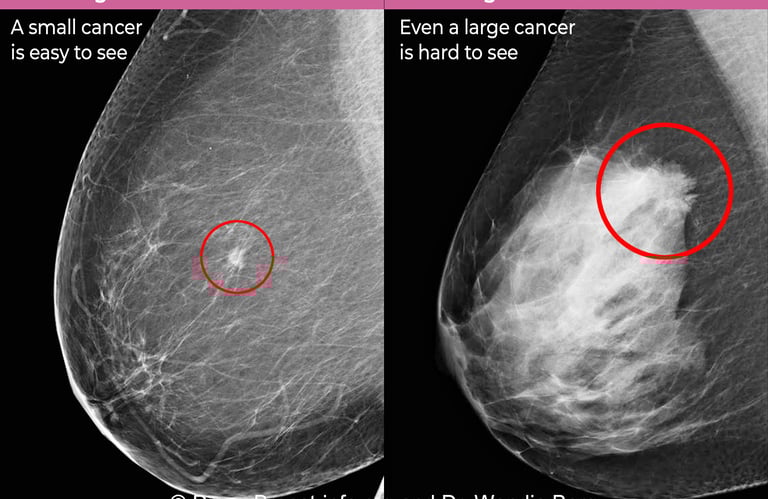

Mamografi (Altın Standart):

Mikrokalsifikasyonlar: LR (+) 15.0. (Özellikle pleomorfik/dallanan tipteyse)

Spiküle Kitle: LR (+) > 20.0.

Tanısal Kör Noktalar: Tomosentez (3D Mamografi) ve Kontrastlı Mamografi (CESM) gibi yeni nesil, LR değeri çok yüksek teknolojilerden bahsedilmeli.